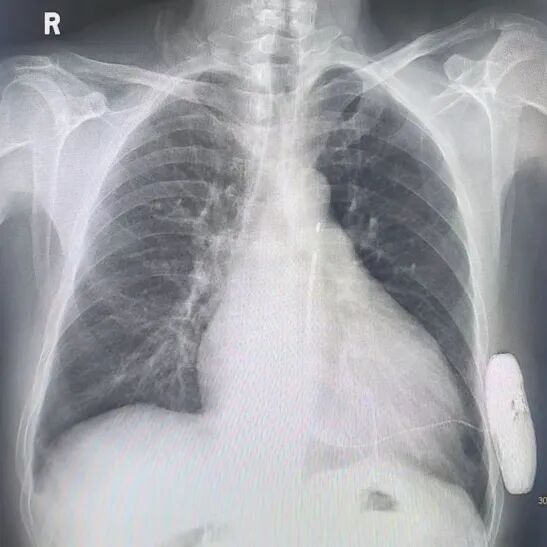

(术后影像)

由于患者EF值低,经讨论后未进行诱颤,经计算PRAETORIAN 评分<90分,无(低)DFT风险,故放弃诱颤。整个手术过程顺利,术后患者生命体征平稳,耗时不到1小时,患者无明显疼痛感觉。术后程控:电学参数正常,系统阻抗70欧姆,除颤线圈紧贴胸骨,除颤器机壳紧贴肋骨,影像完美。患者回病房后,优化各项参数,恢复良好,获得了现场专家团队的高度认可。